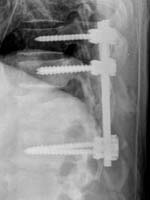

<ôÃßÀü¹æÀüÀ§Áõ>

<¼ö¼úÀü>

<¼ö¼úÈÄ>

¾çÃø

ÇÏÁö ¹æ»çÅëÀ» ÁÖ¼Ò·Î ¼ö¼ú ½ÃÇàÇÑ ¸ð½ÀÀ¸·Î

Ãß°æ ³ª»ç¸ø°íÁ¤¼ú ¹× Ãß°£À¶ÇÕ¼ú½ÃÇà·Ê